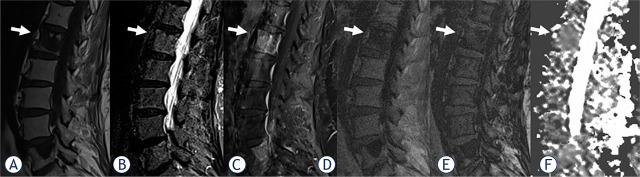

背景:分析化学位移成像(CSI)和弥散加权成像(DWI)这两种非标准磁共振成像(MRI)技术在区分恶性和良性椎体骨髓病变(VBMLs)中的作用:2020年1月至2023年12月期间,使用1.5 T系统对102名肿瘤患者进行了常规脊柱核磁共振成像,随后进行了CSI和DWI成像。从确定的 325 个 VBML 中选出 102 个有代表性的病灶(每个患者一个)。根据组织病理学或成像随访结果,VBML 被分为恶性(n = 74)和良性(n = 28)。VBMLs的定量评估参数为CSI得出的信号强度比(SIR)和DWI得出的表观弥散系数(ADC):结果:与良性 VBMLs 相比,恶性 VBMLs 的 SIR 值明显更高(P < 0.05),ADC 值更低(P < 0.05)。SIR的曲线下面积(AUC)为0.953(p < 0.001),ADC的曲线下面积(AUC)为0.894(p < 0.001)(临界值分别为> 0.82和≤ 1.57x10-3 mm2/s)。SIR 的灵敏度和特异度分别为 93.6% 和 88.5%,而 ADC 的灵敏度和特异度分别为 88.2% 和 92.3%。联合使用 SIR 和 ADC 提高了诊断准确性,其 AUC 为 0.988(P < 0.001,临界值 > 0.19),灵敏度和特异性分别为 100.0% 和 90.9%:由 CSI 和 DWI 这两种非标准磁共振成像技术得出的定量参数 SIR 和 ADC 在区分恶性和良性 VBML 方面显示出了诊断优势。在临床实践中,结合这两种方法可进一步提高脊柱磁共振成像的诊断性能和准确性。

Patients and methods: Conventional spine MRI protocol, followed by CSI and DWI was performed with a 1.5 T system on 102 oncologic patients between January 2020 and December 2023. From the identified 325 VBMLs, 102 representative lesions (one per patient) were selected. VBMLs were divided into malignant (n = 74) and benign (n = 28) based on histopathology, or imaging follow-up. The quantitative parameters for VBMLs assessment were signal intensity ratio (SIR) derived from CSI and apparent diffusion coefficient (ADC) derived from DWI.

Results: The malignant VBMLs had significantly higher SIR values (p < 0.05) and lower ADC values compared to benign VBMLs (p < 0.05). The area under the curve (AUC) was 0.953 (p < 0.001) for SIR, and 0.894 for ADC (p < 0.001) (cut-off at > 0.82, and ≤ 1.57x10-3 mm2/s, respectively). The sensitivity and specificity for SIR were 93.6%, and 88.5%, while for ADC were 88.2% and 92.3% (respectively). The combined use of SIR and ADC improved the diagnostic accuracy to AUC of 0.988 (p < 0.001, cut-off at > 0.19), sensitivity, and specificity of 100.0% and 90.9% (respectively).